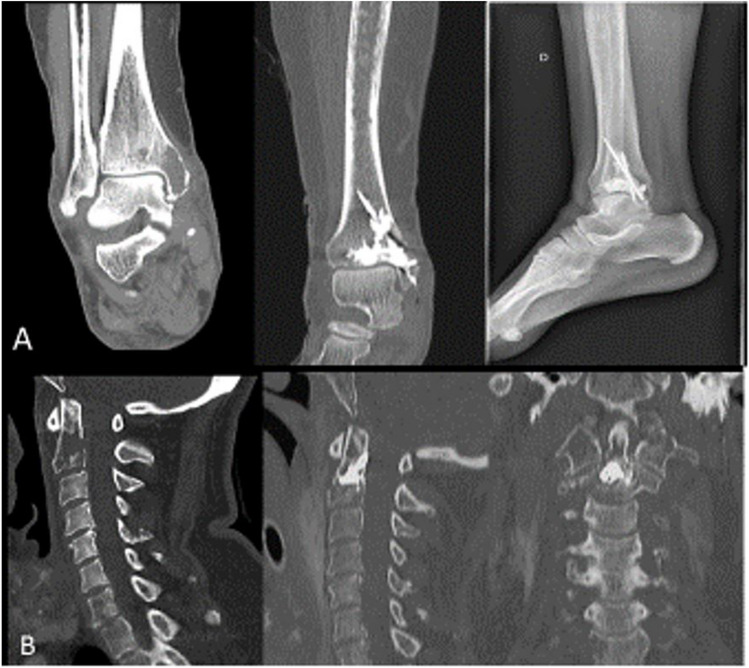

骨是癌症过程中常见的继发部位。骨转移(BM)可能与骨骼相关事件(SRE)相关,如致残性疼痛、高钙血症和导致病理性骨折或脊髓压迫的骨不稳定。SRE导致高发病率和高死亡率,并对经济产生负面影响。BM的现代管理整合了局灶性治疗(如放疗、手术和介入放射学)、矫形器、抗吸收和全身肿瘤治疗。转移导向治疗的选择取决于治疗的目的、患者的特征和对骨病变的完整评估(疼痛、神经风险和不稳定性)。在本文的叙述性回顾中,我们旨在提供最新的文献总结,描述当前和新兴的BM多模式治疗策略的优缺点,并基于这些数据,提出BM管理的更新算法。

Bone is a common secondary site of dissemination during the course of cancer. Bone metastases (BM) can be associated with skeletal-related events (SRE) such as disabling pain, hypercalcemia, and bone instability that leads to pathological fractures or spinal cord compression. SRE contribute to high morbidity as well as, mortality, and have a negative economic impact. Modern management of BM integrates focal treatments (such as radiotherapy, surgery, and interventional radiology), orthoses, and antiresorptive and systemic oncological treatment. The choice of a metastasis-directed therapy depends on the objective of the treatment, the patient characteristics, and the complete assessment of the bone lesion (pain, neurological risk, and instability). In the narrative review present herein, we aim to provide an updated summary of the literature, with description of the advantages and disadvantages of current and emerging strategies in the multimodal treatment of BM and, based on these data, an updated algorithm for the management of BM.